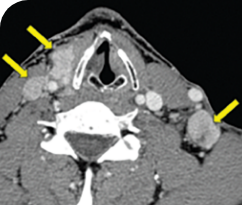

56-YEAR-OLD FEMALE WITH MULTIPLE METASTASES3

- 56-year-old female with PTCa that had metastasized to multiple sites, including the brain

- PRa after 4 weeks on VITRAKVI® (larotrectinib); CRa after 8 weeks

Clinical presentation1

- Patient was assessed to have metastatic, rapidly progressive, RAl-refractory PTC based on imaging that revealed multiple metastatic sites, including the neck, mediastinum, lung, scalp, and bones

- Biopsy of a scalp lesion helped to confirm the PTC metastasis

- Metastases to the brain and liver were observed after progression on systemic treatments

Response to VITRAKVI1

- After 8 weeks on VITRAKVI, all target lesions had disappeared, demonstrating a complete response

- The complete response was sustained over 11 months of treatment with VITRAKVI

Response in primary and metastatic lesions1

MRIa imagery of the lungs. Arrow indicates large target lesion in left lung.1

SCAN 1: LUNG

MRIa imagery of the brain. Arrow indicates large target lesion in left lung.1

aMRI, magnetic resonance imaging.

Images courtesy of Dr Fabian Pitoia.